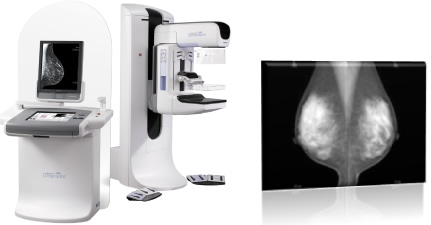

マンモグラフィー検査とは

当センターでは2004年よりデジタルマンモグラフィー装置が導入されています。フィルムを使用せず、撮影直後にモニター上に画像を映し出すことができ、短時間で高画質の画像を得ることが可能です。乳腺内の腫瘤や石灰化の有無を調べるため、乳房を押さえ、薄く伸ばした状態で撮影を行います。多少の痛みを伴う検査ですが、乳房を圧迫することによってより情報量が増え、被ばく量も低減できます。

2007年に日本乳がん検診精度管理中央機構が定める「マンモグラフィー検診施設画像認定」を取得しており、マンモグラフィー装置・画像・被ばく線量ともに基準を満たしていることが認められています。さらに精度の高い検査を行うために、「検診マンモグラフィー撮影診療放射線技師認定」取得者を中心とした女性技師が行っていますので、安心して受診していただけます。